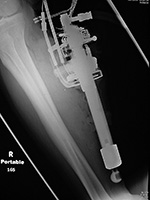

| Retained drill guide |

| Frontal and lateral views of the right wrist after placement of a volar T-plate and screws for a comminuted distal radius fracture. On the lateral view there is a retained drill guide (arrow) that was inadvertently left in place. It should have been removed at the end of the surgical procedure. It is not evident on the AP view and was initially overlooked by both an MSK radiologist and the patient's orthopedic surgeon. |